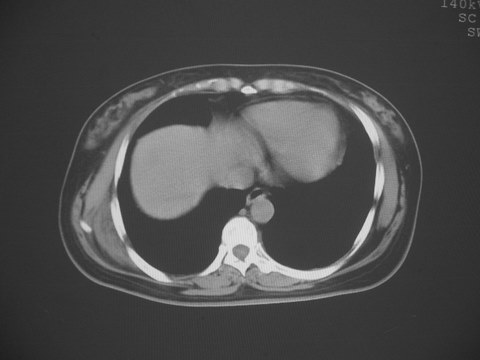

无意中发现右背部肩胛下缘半球状突起,无红,热,痛感觉。拍平片未见异常。ct发现右肩胛下角深层新月型软组织肿胀,ct值-50至15,大家看看是什么性质,来源,初步考虑来源于下后锯肿,考虑下后锯肌肿胀,可是病人无明确外伤史,也不疼痛

三、弹性纤维瘤影像

典型位于背部,在肩胛下角和胸壁软组织之间,肿瘤表面为菱形肌和背阔肌所被覆深部,紧邻肋骨和肋间肌,呈半圆形或扁豆状,宽基底与胸壁相交,边界比较清楚,相邻的肌肉和肋骨无侵蚀,部分病变与其表面的临近肌肉之间可受压呈弧形的脂肪界面,肿瘤周围软组织无水肿。

从mr表现可以推断ct影像,即肿块呈软组织密度,病灶内可出现脂肪密度的低密度影。